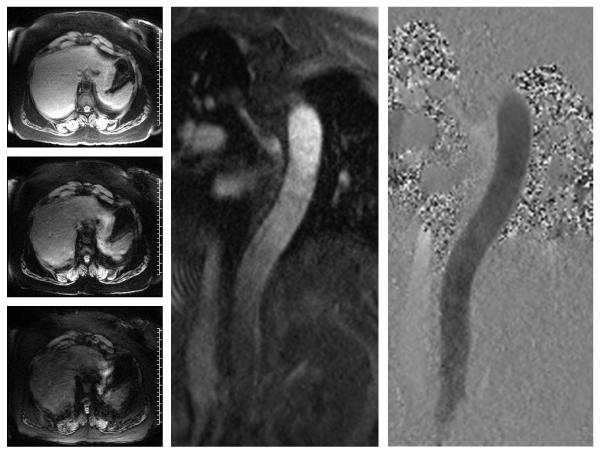

| Figure 1: Left panels: Images obtained at serial echo times (top: 1.9 ms, middle: 5 ms, bottom: 8.1 ms) from a tranverse plane abdominal multiecho gradient echo acquisition show the images used for liver T2* computation, a wellvalidated noninvasive technique to estimate liver iron content. In the absence of secondary causes of hepatic iron overload, liver iron content may be considered a suitable surrogate for total body iron. Middle panel: magnitude image showing a longitudinal section of the descending aorta. Right panel: velocity-encoded image showing in-plane velocities in the descending aorta, from which pulse wave velocity is calculated. |